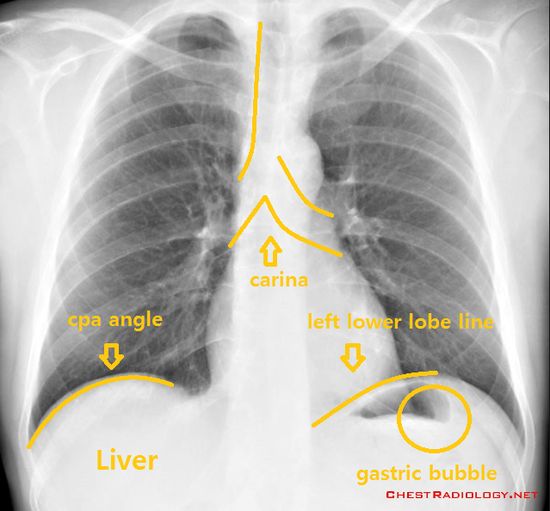

Xray 판독법 (carina, CPA angle, gastric bubble, Bowel perforation) 네이버 블로그 Identifying Carina On X Ray The trachea passes to the right of the aorta and so may be. It is therefore important that you can confidently assess a chest radiograph and detect abnormalities, especially those that are life threatening. Trachea, carina, bronchi and hilar structures. How to find the carina on a frontal chest radiograph • follow the right or left main bronchus backward until. Identifying Carina On X Ray.

Xray 판독법 (carina, CPA angle, gastric bubble, Bowel perforation) 네이버 블로그 Identifying Carina On X Ray The carina is a cartilaginous ridge at the tracheal bifurcation, serving as an important reference point in chest imaging. Correct positioning of a cvc tip. It is therefore important that you can confidently assess a chest radiograph and detect abnormalities, especially those that are life threatening. The trachea passes to the right of the aorta and so may be. How. Identifying Carina On X Ray.